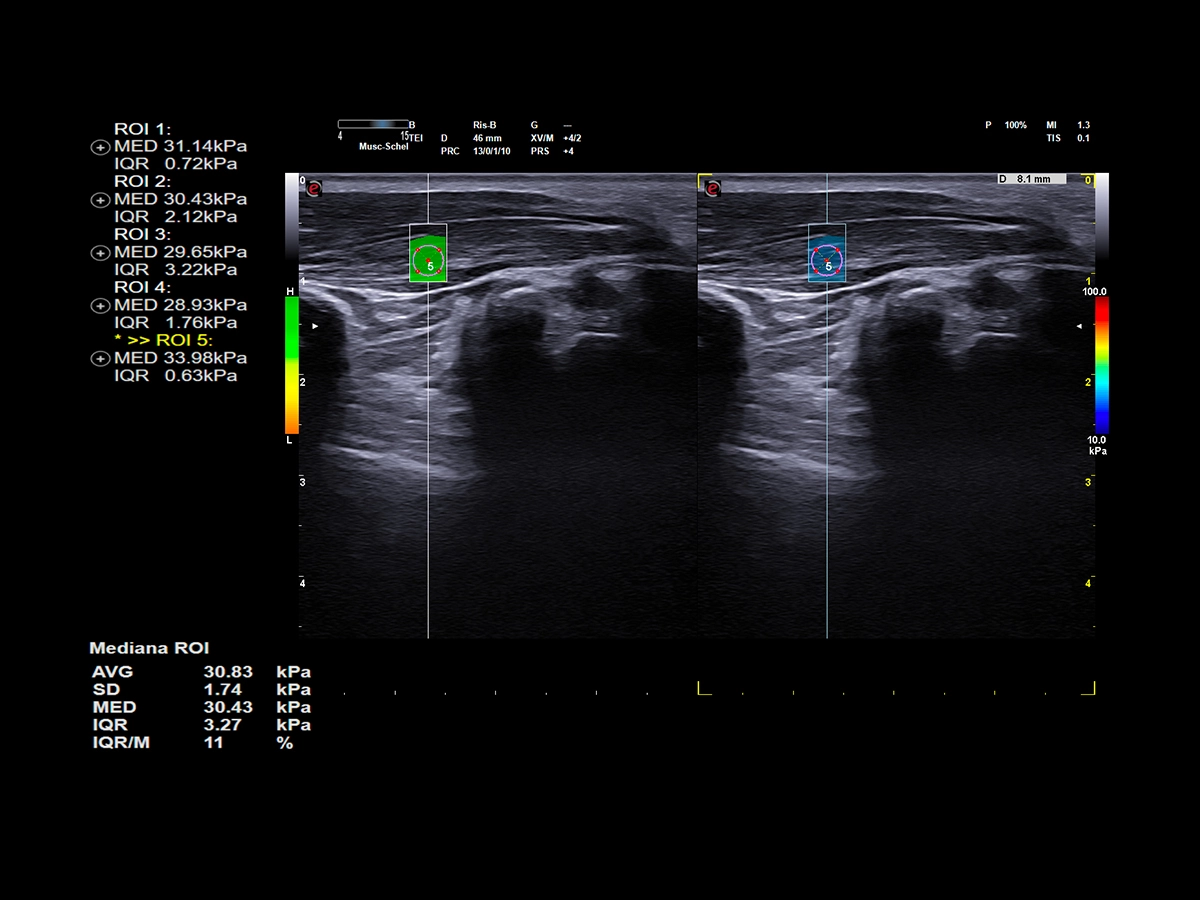

Elastosonography is particularly important in musculoskeletal applications because it provides valuable information about the mechanical properties of soft tissues in the musculoskeletal system. The ability to assess tissue elasticity is crucial in the diagnosis, monitoring, and management of various musculoskeletal conditions. ElaXto is the Esaote real-time, non-invasive strain elastography tool that allows you to assess tissue stiffness at a glance, thanks to a colour-coded stiffness mapping. Instead, QElaXto 2D, shear-wave elastography, is an Esaote technology that provides an immediate quantitative value of tissue elasticity, which can be particularly interesting in the follow-up of tendon injuries.